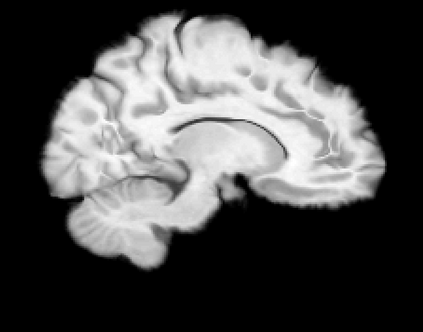

The purpose of this work is to contribute to the state of the art of deep-learning methods for diffeomorphic registration. We propose an adversarial learning LDDMM method for pairs of 3D mono-modal images based on Generative Adversarial Networks. The method is inspired by the recent literature for deformable image registration with adversarial learning. We combine the best performing generative, discriminative, and adversarial ingredients from the state of the art within the LDDMM paradigm. We have successfully implemented two models with the stationary and the EPDiff-constrained non-stationary parameterizations of diffeomorphisms. Our unsupervised and data-hungry approach has shown a competitive performance with respect to a benchmark supervised and rich-data approach. In addition, our method has shown similar results to model-based methods with a computational time under one second.